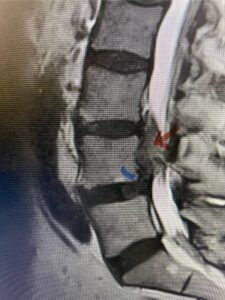

The next patient is a 56-year-old morbidly obese female who had progressive leg pain and weakness. She was over 320 lbs and did not have diabetes either. On MRI she had a massive disc herniation spanning the L3-4 and L-4 interspaces, centered behind the L4 vertebral body (Fig 3A and B). She also had an L4-5 spondylolisthesis. There were opinions that the disc emanated from the L3-4 disc space, but because of spondylolisthesis and on careful inspection of the MRI, there was a high chance the disc herniation had instead emanated from L4-5 (Fig 4). She had conservative treatment including epidurals but had worsening strength and numbness. She was scheduled electively for surgery, but then fell, and broke her ankle. She could not walk, particularly due to the pain down her leg. She was taken to the operating room urgently after she was cleared medically. She had no issues cardiologically and was taken to the operating room. The patient underwent a laminectomy that extended above the L3-4 disc space to below the L4-5 disc space. We encountered mainly centered on the left at the level of the L4 vertebral body and massive disc herniation that created a huge cavity in the lumbar canal. It was covered in an interesting thin membrane that we dissected off the disc herniation (Fig 5). Postoperatively the patient did experience significant relief of pain, but some improvement of strength. In combination with the ankle fracture and the extent of preoperative weakness, the patient required extensive rehab. The patient also developed a seroma and some wound drainage issues that were treated locally.

Fig. 3a : Sagittal T2-weighted lumbar MRI demonstrating a massive L4-5 disc herniation with superior migration behind the L4 vertebral body and taking up most of the left side of the spinal canal (red arrow) Note the slight grade one spondylothesis at L4-5 (blue dash). Notice the severe compression of the thecal sac (blue arrow) by the large left sided disc herniation (red arrow)